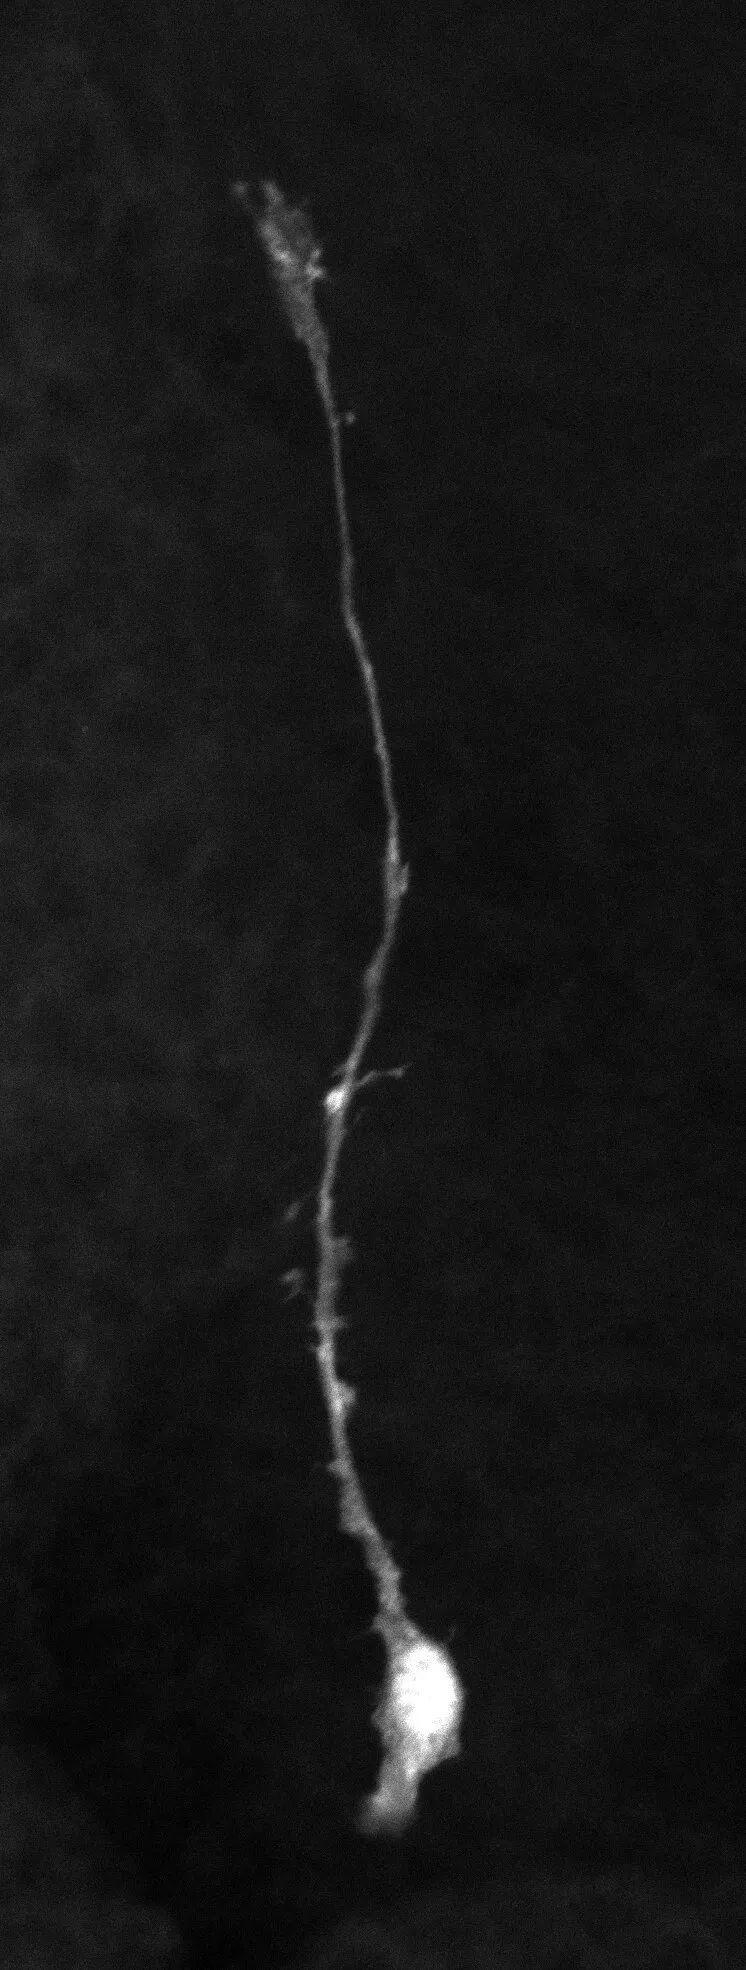

图片

脑室-脑室下区的出生后神经干细胞(NSC)。大多数出生后 NSC 保持静止状态,可以长期维持。出生后谷氨酰胺代谢的改变是出生后 NSC 获得静止所必需的。Credit: Nagoya City University Graduate School of Medical Sciences

研究团队首先对足月鼠和早产鼠的脑室-室下区(ventricular-subventricular zone, V-SVZ)进行代谢组学分析,发现正常出生时Glul基因表达激增,促使谷氨酸转化为谷氨酰胺,驱动放射状胶质细胞(radial glia, RG)进入静止状态。在早产模型中,该代谢通路受阻导致RG通过mTORC1信号通路(细胞生长调控系统)持续活跃,短期内神经发生增加40%,但成年后干细胞库减少60%,神经发生量下降至正常组的30%。人类尸检显示,早产儿V-SVZ区新生神经元标志物DCX阳性细胞减少55%。通过慢病毒载体调控Glul表达证实,该基因在出生时的精准激活是维持干细胞休眠的关键。研究发表在 Science Advances 上。